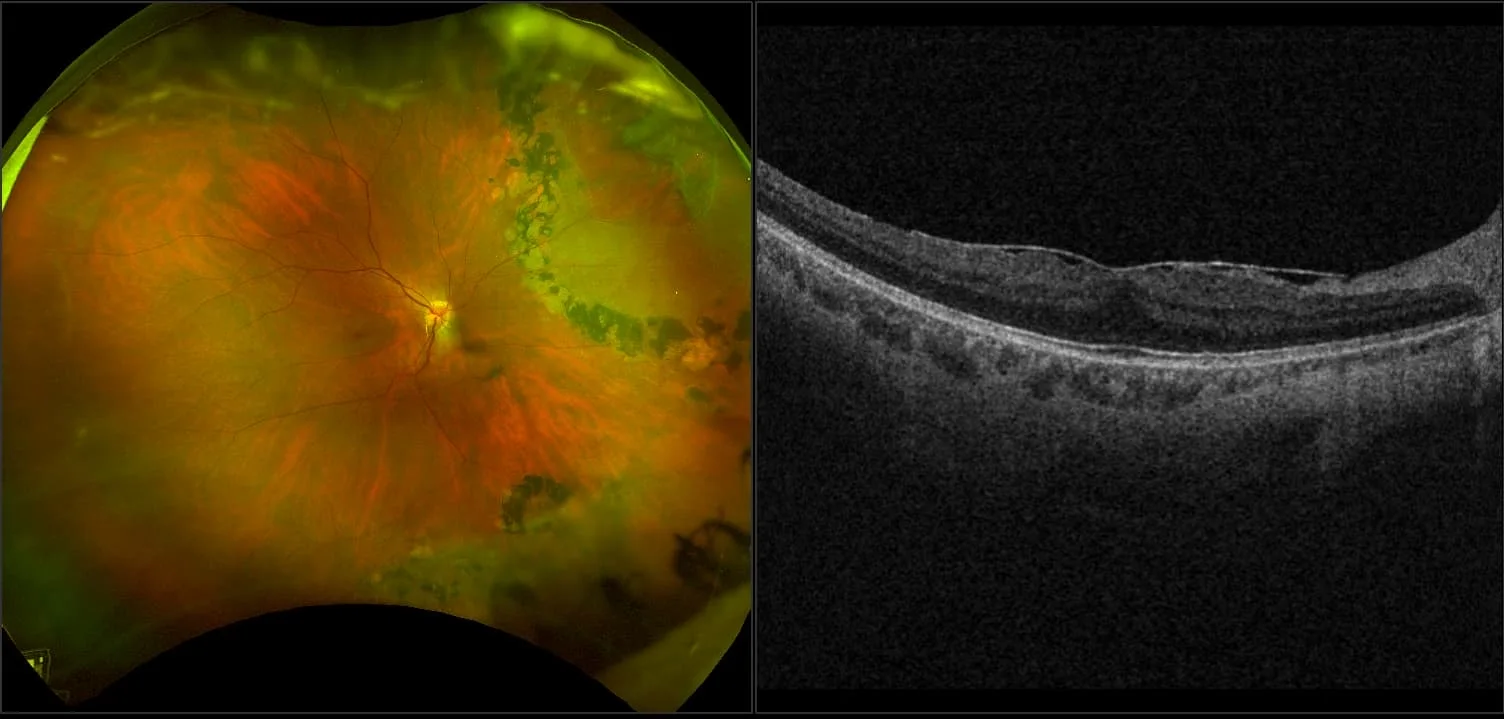

MonacoPro - Retinal Detachment, RG, AF, OCT

A retinal detachment (RD) is the separation of the sensory retina from the Retinal Pigment Epithelium (RPE) (outer segments of the photoreceptors from the microvilli of the RPE).